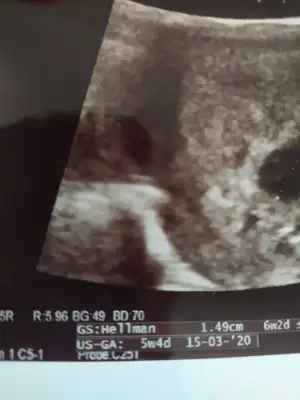

Var canım GS yazan kısımPerşembe günü gittim canım doktora 5+4 dedi kese kaç mm bilmiyorum ki verdiği ultrason fotoğrafında var mıdır acaba

GS yazan kısım 1.49cm yazıyor olması gerekenden fazla mı yani anlayamadımVar canım GS yazan kısım

Evet 14 milim oluyor doktor anormal bi durumdan bahsetmedi ama korktum şimdi1.49 yazan işte ama tam anlamdım valla 14 milim mi oluyo o benım ki. 0.64 milim di